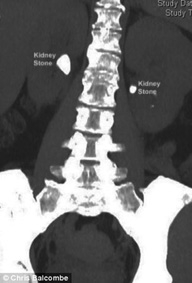

Phương pháp mới cho phép tán sỏi ở hai thận cùng lúc